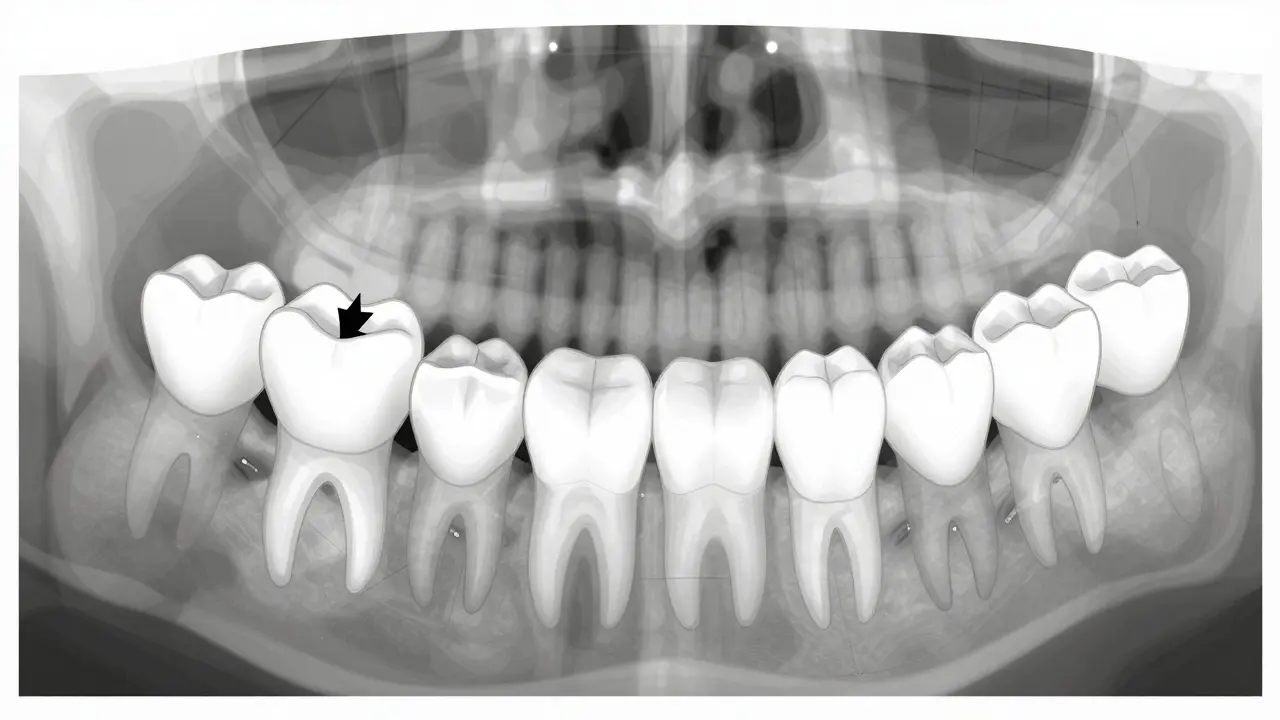

Schematický pohled na pozici prvního trvalého moláru za mléčnými zuby.

V těchto případech je potřeba rentgenové vyšetření. U dětí se používá panoramický snímek, který ukazuje všechny zuby najednou - i ty, které ještě nejsou vidět. Tento snímek je bezpečný a trvá jen pár sekund. Výsledky pomohou zubaři rozhodnout, zda je třeba zásah, nebo zda je vše v pořádku.